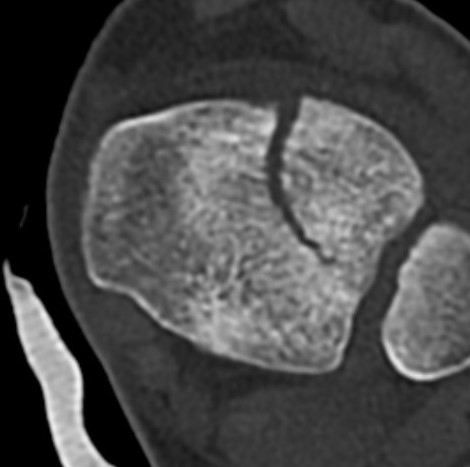

CT

Coronal images: Salter-Harris type III

Sagittal images: Salter-Harris type II

Axial images: 3 point star